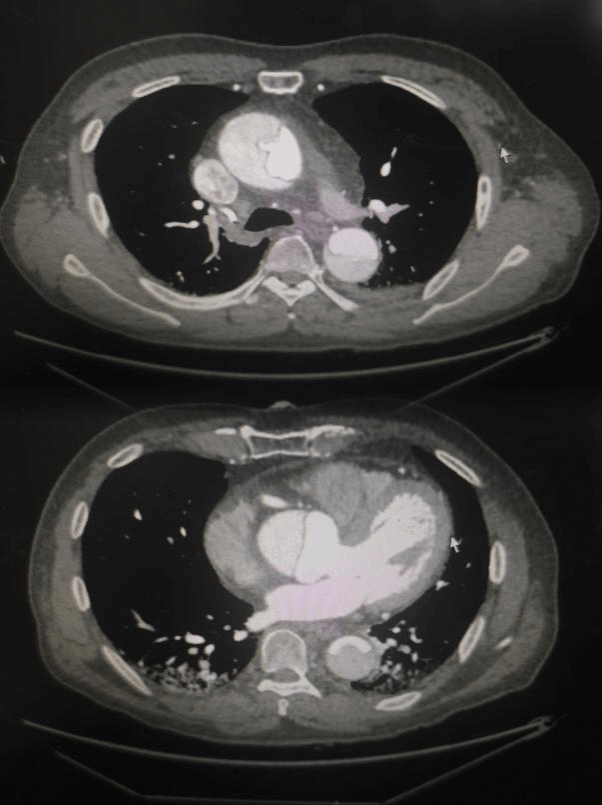

患者韩先生下午突发胸背部剧烈疼痛,呈撕裂样,当地医院处理后仍不能缓解,遂紧急送至西安交大二附院心血管病院。心内科张岩教授凭着丰富的临床经验,收入院后立即行急诊主动脉CTA检查,确诊为"Stanford A型主动脉夹层",血管内膜撕裂已延伸至升主动脉,随时可能破裂导致猝死。"这类患者48小时内死亡率超过50%,必须立即手术!"遂转入心血管外科。心血管病院副院长高峰教授迅速集结心外科团队,并紧急联系麻醉科、手术室、输血科等相关科室,在多学科联动下,成功启动"绿色生命通道"。凌晨12点紧急为患者进行了主动脉瓣成型+升主动脉置换+Sun’s手术。清晨7点,随着体外循环机缓缓停机,患者心脏重新有力跳动。术后转入心脏重症监护室,第二天即拔除气管插管,术后第四天转入普通病房。